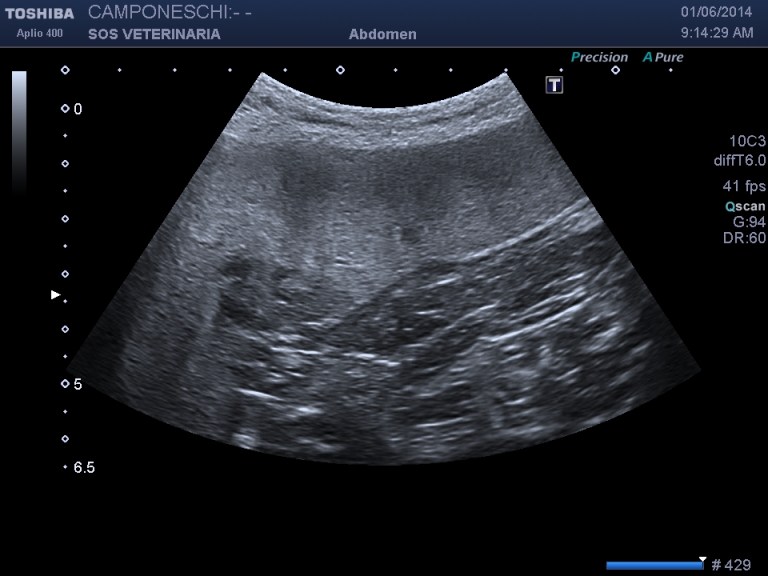

Beagle maschio 13 aa di nome Teo ,insorgenza iperacuta dopo trauma di lieve entita’ (caduta da un muretto alto meno di 1 metro) di sindrome algica addominale acuta ,l’esame ecografico mostra massa irregolare , disomogenea perirenale sx profilo d’organo irregolare e alterato con severa perdita di tessuto corticale ,quadro compatibile con grave infarcimento necrotico- emorragico , eseguito esame ceus ,ha confermato l’avascolarita’ della lesione ,in diagnosi differenziale e’ stato considerato emangiosarcoma renale con rottura secondaria al trauma .

milza lesione focale eterogenea

La minima entita’ del trauma ci ha fatto sospettare un emangiosarcoma allo stesso modo di quello splenico in pronto soccorso molto comune alla presentazione . dopo stabilizzazzione di 48 ore e’ stata eseguita nefrectomia .L’esame istopatologico ha escluso un emangiosarcoma e diagnosticato un grave e severo infarcimento necrotico-emorragico con distruzione del 30 % della massa renale ,si ipotizza la rottura di una anomalia presistente forse vascolare per la minima entita’ del trauma che non spiegherebbe se non come eccezione la gravita’ del quadro ..